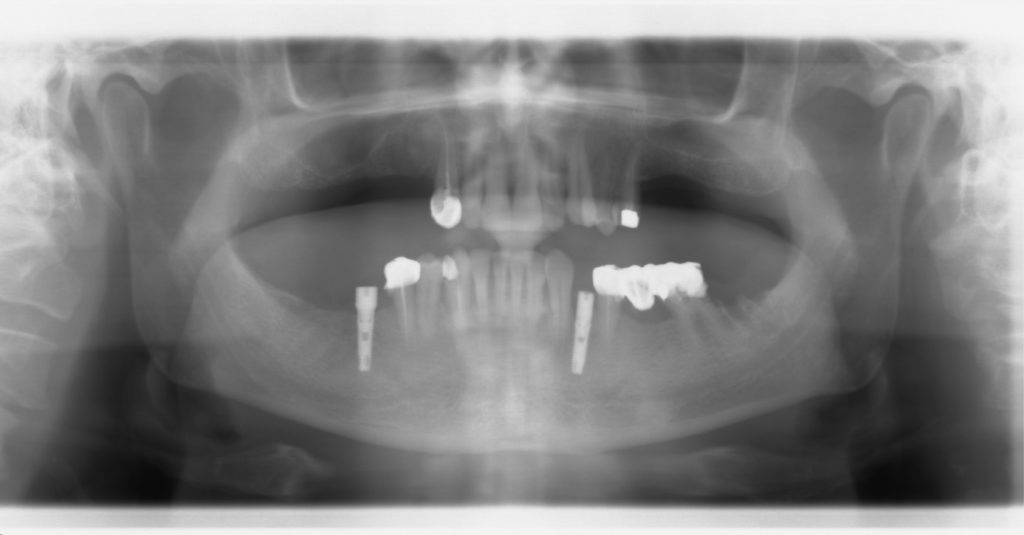

First panoramic radiograph (initial condition) presented by the patient.